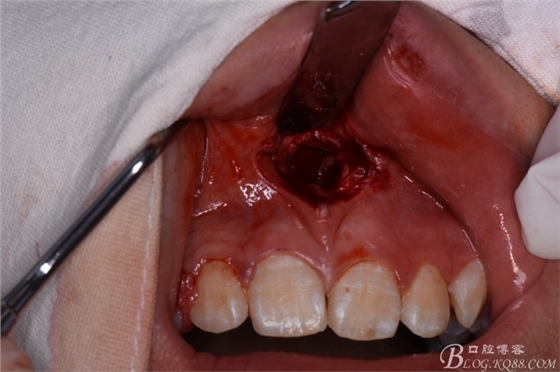

圖20. 在12、13根尖所對應(yīng)的前廳溝處做第二個弧形切口

圖21.一定要切透粘骨膜。

圖22.翻瓣、暴露骨面

圖23.去骨、暴露出鼻底下方的倒置多生牙。